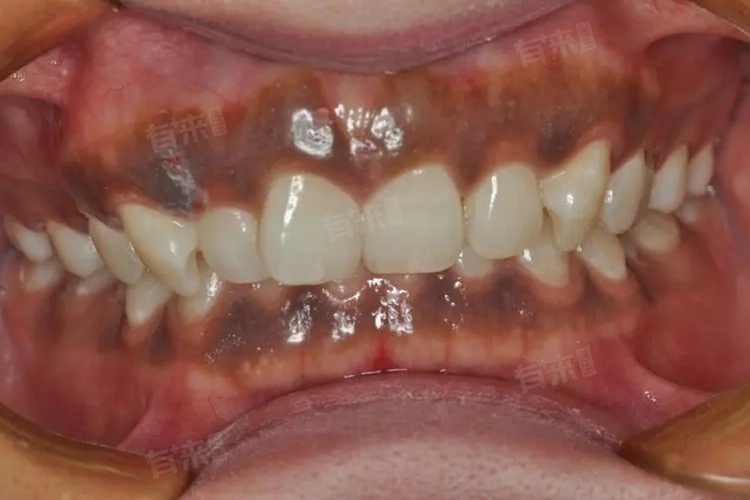

牙龈发黑这一现象可能是由于色素沉着、牙结石等因素导致的,建议存在此类问题的患者及时就医检查诊断,并在医生的建议下进行针对性的治疗。

1、色素沉着:色素沉着是导致牙龈发黑最常见且最轻微的原因,其通常是由于长期摄入含有大量色素的食物或饮料,如浓茶、咖啡、紫菜、油菜等,或者长期吸烟所致,色素会附着在牙龈上,逐渐形成一层黑色的膜。

2、牙结石:牙结石是牙齿表面和牙龈边缘的一种矿化物质沉积,主要由食物残渣、细菌和唾液中的矿物质构成。如果长时间不进行口腔清洁,牙结石会逐渐积累并变黑,从而透过较薄的牙龈透出黑色。

3、烤瓷牙金属染色:如果患者镶嵌了烤瓷牙,而烤瓷牙中的金属材料长期与唾液反应,可能会释放出金属离子,会刺激牙龈,导致牙龈发黑。

4、黏膜黑斑:黏膜黑斑是一种口腔黏膜上的色素性病变,可能由黑色素细胞数目增多或激素分泌异常等因素导致,多发于牙龈、硬腭、颊黏膜等部位,表现为黑色的斑点或斑块。

5、牙龈炎:牙龈炎是牙龈组织的一种炎症性病变,通常由牙菌斑、牙结石等刺激因素引起。当牙龈炎发生时,牙龈会变得红肿、出血,并可能伴有疼痛去,且在严重的情况下,牙龈炎可能导致牙龈组织坏死和发黑。